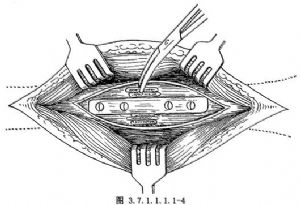

從髂骨或脛骨切取長方形骨板,修整使之能平整服貼放在已鑿去薄層皮質骨的脛骨受骨區面上。用持骨鉗夾住骨折上下端與骨塊,用骨鑽鑽通植骨塊和脛骨兩側骨皮質,然後再用4~6枚螺釘固定,緊密植入大量松質骨(圖3.7.1.1.1.1-4)。